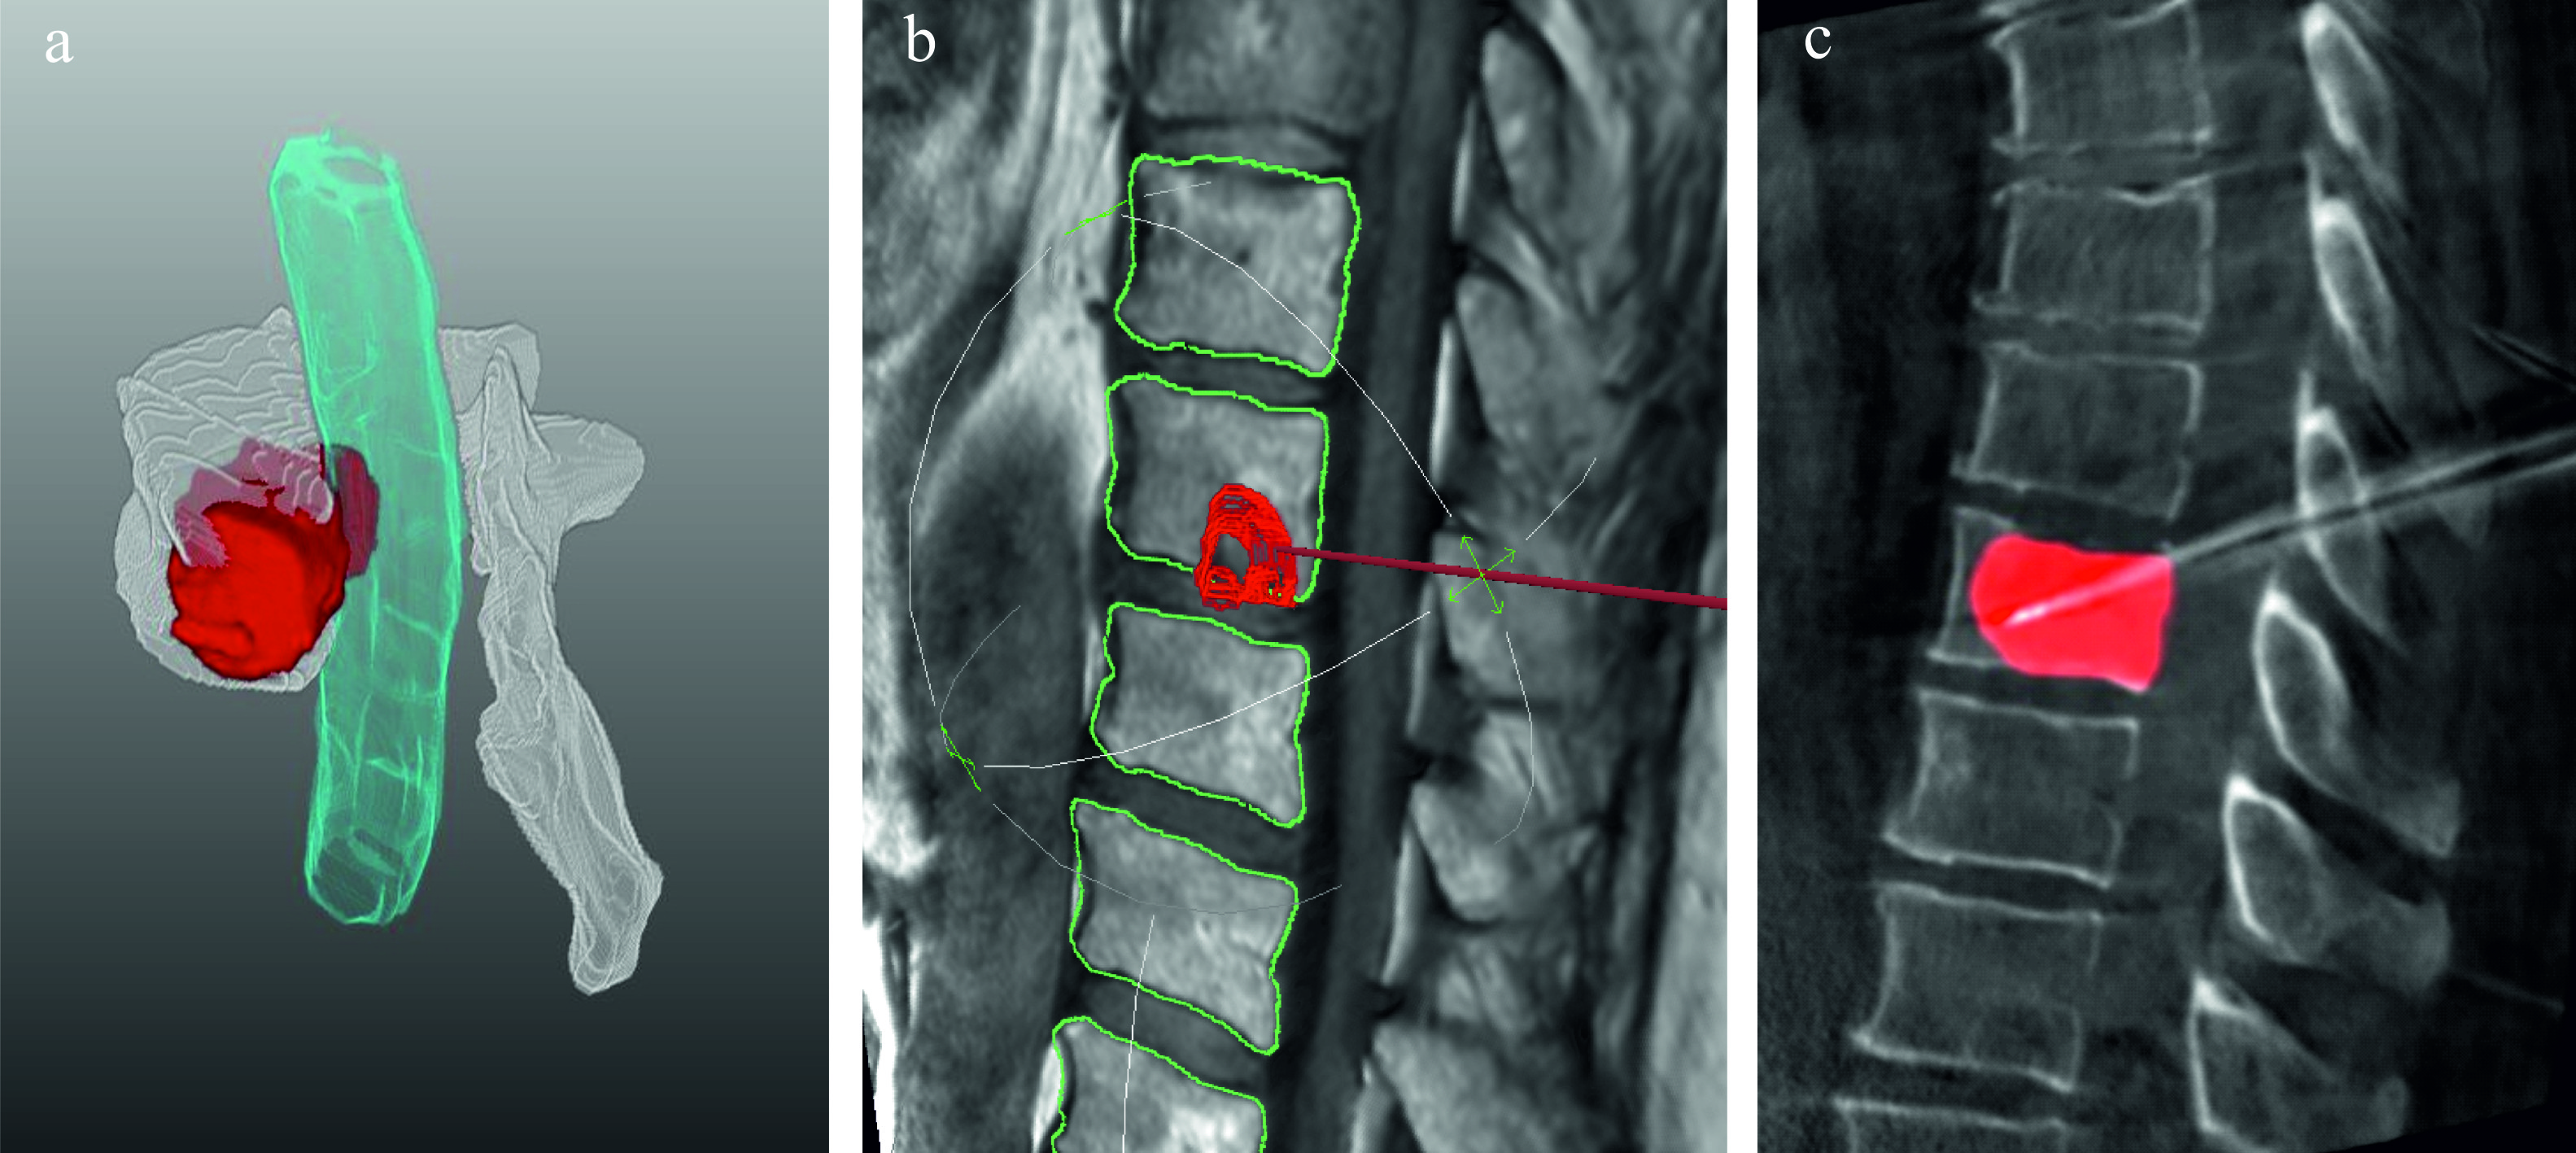

With regard to minimally invasive image-guided interventions like radiofrequency ablation (RFA), the segmentation of vertebral metastases constitutes an essential prerequisite for various workflow steps, starting from therapy planning, over the intervention procedure, up to the treatment outcome validation (see Fig. 2). First of all, it enables a detailed assessment of extent, shape and spatial relations of the metastases with surrounding risk structures and thus supports the planning of access pathways and positioning of minimally invasive applicators. In addition, patient-individual simulations of RFAs, i.e. ablation zone predictions are based on these segmentations weihusen2010towards ; kroger2006numerical . Pre-interventionally produced segmentation masks used as overlays onto the intra-operative images can enhance navigation w.r.t. accuracy and time required for metastasis puncturing and therefore, have a beneficial effect on the treatment outcome. Finally, after image registration of pre- and post-operative MRI scans, quantitative outcome validations are made feasible by matching the segmentation masks of metastases and necrosis zones. A computer-assisted approach could save time during routines and recurrent procedures and relieve the workload of radiologists, since segmentation of volumetric image data is time-consuming and fatiguing given the large number of image slices and sequences acquired per patient.

Refer to caption

Figure 2: Segmentation of spinal metastases could support multiple procedures throughout the therapeutic workflow: intuitive visualisation of spatial relations to risk structures (a) and applicator pathway optimization (b) while intervention planning, as well as navigation support and visual target zone enhancement during the intervention (c).